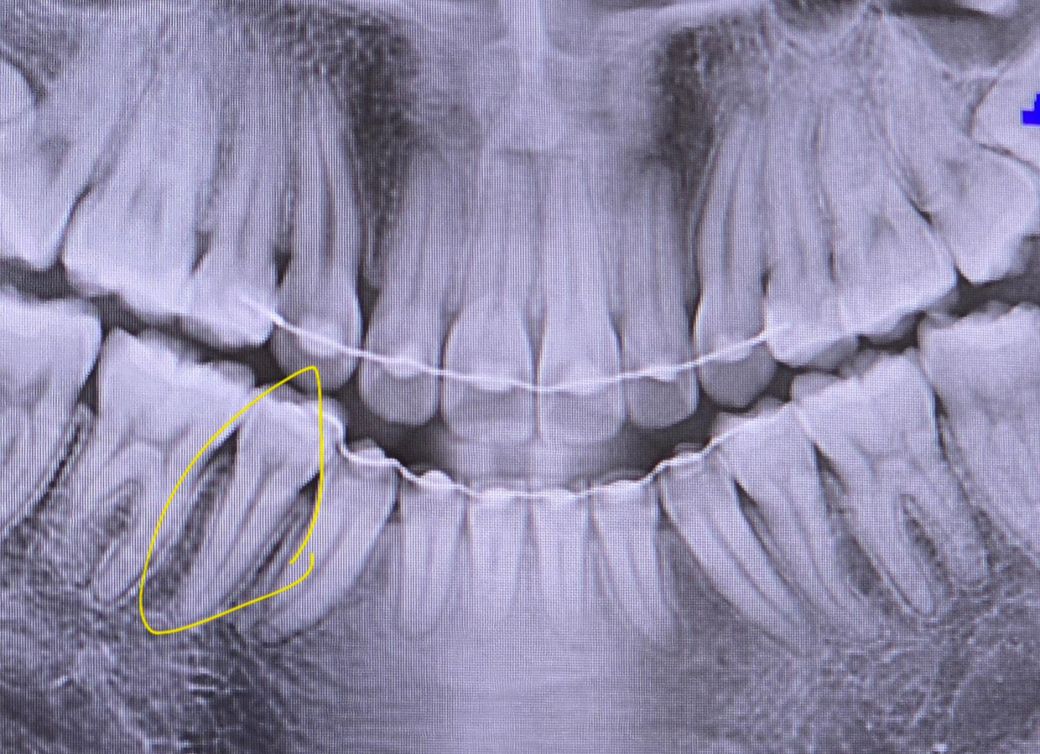

사랑니 전문 병원에서 2년전 사랑니를 빼기 전에 찍은 사진 (1) 과 2년 후에 사랑니를 빼고 나서의 사진 (2) 사이에 교정기를 단 쪽에 뭔가 파여 있는 듯 한 자국이 보이더군요... 그래서 1개월 뒤 타 치과에서 검진(3)을 받아봤는데 충치는 없다고 진단해주셨습니다... 원래도 시림 증상도 없고 멀쩡해서 안심이긴 하지만 타 선생님이 보시기에도 충치가 아닌지 궁금합니다 ㅜ 점점 신경 쪽하고 가까워지고 있는 것 같기도 해서요...🥺

파노라마 엑스레이는 다양한 왜곡, 음영이 있어서 판단이 어렵고요 충치 의심 부위에 치근단 엑스레이를 찍어봐야합니다

사진으로 보이는 부위는 방사선사진이 어둡게 보이는 곳입니다. 인접면의 충치를 정확하게 판단하기 위해서는 치근단사진이나 육안검사가 필요할 것으로 생각됩니다.

방사선 사진에는 치경부 소환 이라는 것이 있는데요 말씀하신 치아의 목 부위(머리와 뿌리 사이)가 다른 곳 보다 더 까맣게 보이는 것입니다. 일종의 착시현상같이 저렇게 보이는 것인데 사진을 찍을때마다 심하기도, 정상으로 보이기도 합니다. 육안으로 봤을때 괜찮고 증상이 없으시다면 크게 걱정하지는 않으셔도 되겠습니다.

사진상으로는 충치가 깊어 보이거나 그렇진 않습니다. 지금처럼 관리를 잘하시면될것같습니다.